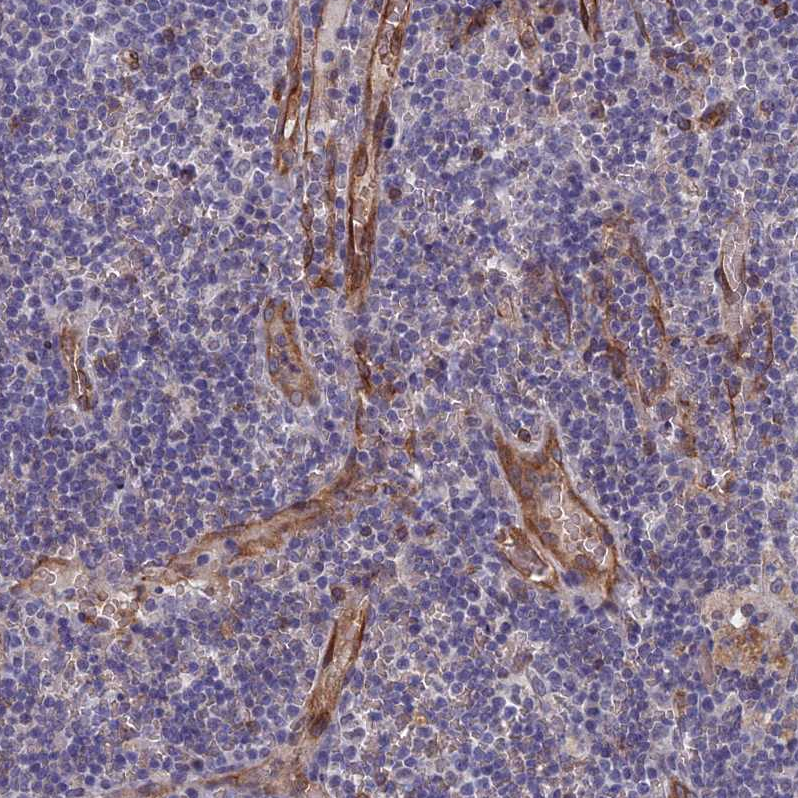

Immunohistochemical staining of human placenta shows moderate membranous-cytoplasmic positivity in endothelial cells.